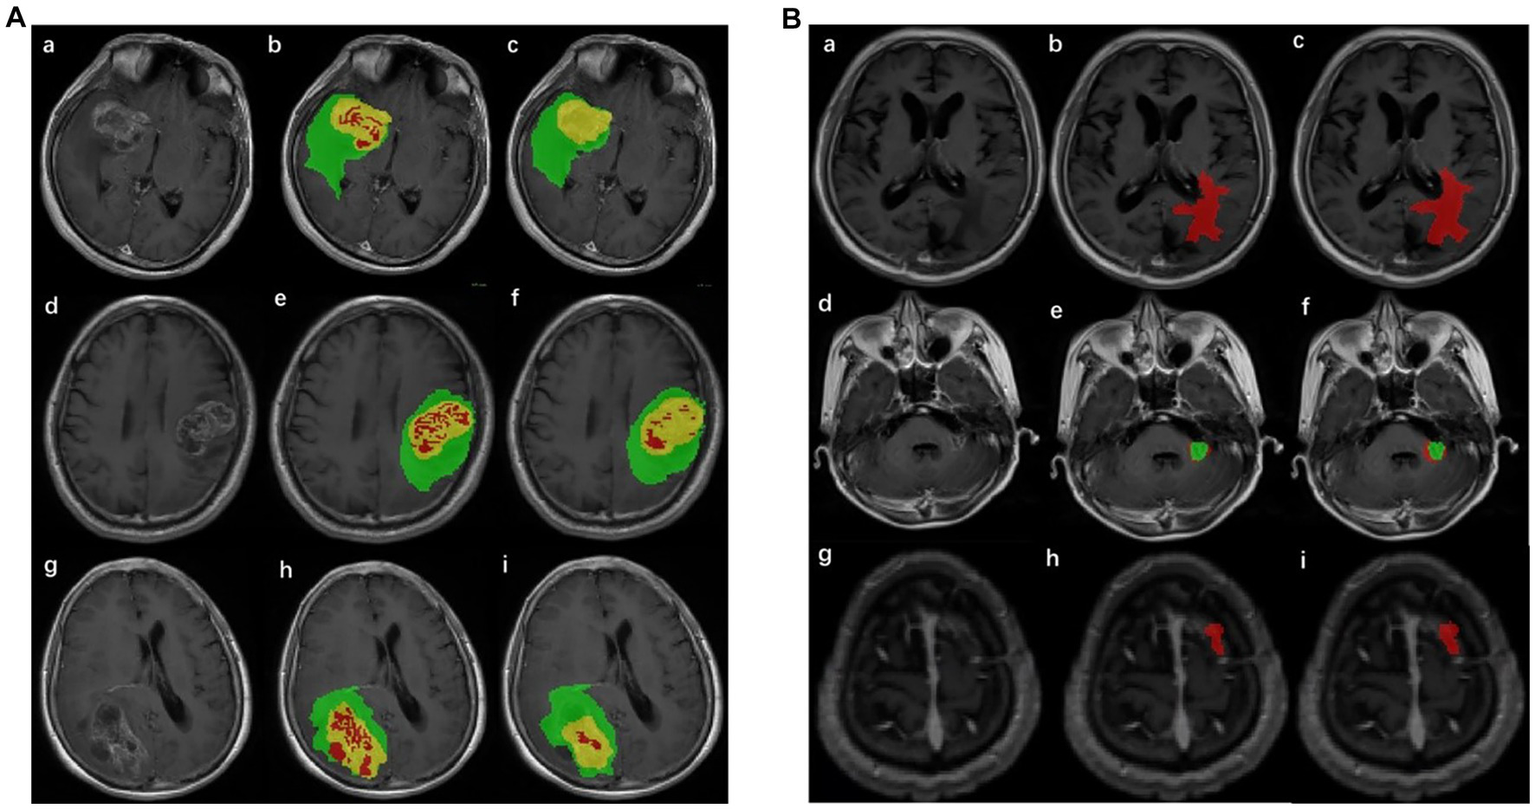

The annotation of the tumor ROI is the preparation for tumor classification. It was difficult to segment glioma and Mets lesions by only one segmentation model; thus, two segmentation models were implemented in the pipeline. The structure of the improved segmentation model is detailed in Supplementary Figure S1. Two models were based on revised U-net (30) architecture, incorporating the DenseNet (31) and self-attention (32) and used T1-CE and T2-flair images with sizes of 160 × 160 × 16 as network inputs. The glioma segmentation model yielded three regions including enhancing tumor, necrotic tumor, and peritumoral edema. The Mets segmentation model yielded two regions including enhancing tumor and peritumoral edema. These regions were compatibly applied to both MRI sequences (T1-CE and T2-flair). The whole ROI was the combination of these regions and was merged for subsequent quantitative feature extraction. The result of the automatic lesion segmentation is shown in Figure 2.

Figure 2

Result of lesion automatic segmentation. (A) Result of gliomas: green label indicates enhancing tumor, yellow indicates peritumoral edema, and red indicates necrotic tumor area. (a), (d), and (g) were original MRIs; (b), (e), and (h) were ground truth; (c), (f), and (i) were the results of the segmentation model of gliomas. (B) Result of Mets: red label indicates peritumoral edema and green indicates enhancing tumor. (a), (d), and (g) were original MRIs; (b), (e), and (h) were ground truth; (c), (f), and (i) were the results of the segmentation model of Mets.